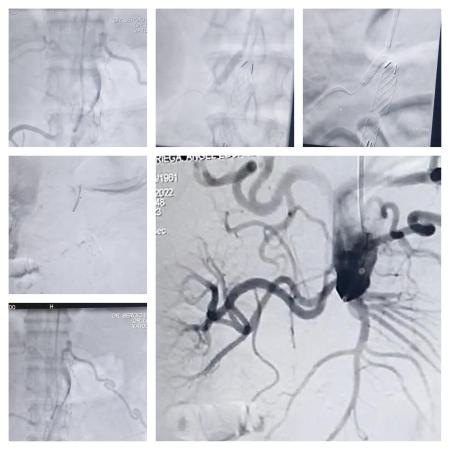

El procedimiento fue realizado por un equipo de profesionales del INCOR conformado por los Dres. Sergio Ludueña, hemodinamista, y Alejandro Flores, cirujano vascular.

Al respecto, el Dr. Sergio Ludueña informó que la intervención fue realizada a un fumador severo de 62 años, que contaba con un importante deterioro, tanto a nivel respiratorio como a nivel vascular, con obstrucciones coronarias en arteras periféricas y epoc.

En ese sentido, el profesional de la salud manifestó: “Tenía síndrome de Leriche, que es lo que tratamos”, y continuó: “Tenía ocluida totalmente la aorta a nivel del nacimiento de la única arteria renal, porque la otra se había tapado”.

“Era un paciente complejo al que hubo que solucionarle primero el problema de las arterias coronarias. Le colocamos 4 (cuatro) stend en las arterias del corazón, y abordamos la recanalización de la arteria aorta”, detalló Ludueña.

Procedimiento

El Dr Sergio Ludueña explicó: “Nosotros ingresamos por el brazo hasta la ingle derecha con catéteres y cuerdas. Los elementos van abriendo el paso para dilatar con balones en forma progresiva, y posteriormente se le coloca la endopróteisis para impermeabilizar la aorta. Con esto generamos un eje de flujo hacia la pierna derecha”.

“Una vez que se abre eso, se realiza un bypass que va a cruzar a la otra pierna para lograr una perfusión que permita mejorar la calidad de vida del paciente, mejorando la circulación en sus extremidades, ya que el paciente se encuentra en silla de ruedas”, afirmó el hemodinamista del INCOR.